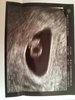

Po wizycie! Termin wg usg 30.03.2019r.

Poza tym mam torbiel na jajniku, do obserwacji i "odwarstwienie jaja płodowego od u.w. i ściany przedniej", ale to podobno na początku może się zdarzyć i jest ok. [emoji3]

Najważniejsze, że jest serducho :)

Moje maleństwo ma 4 mm, serduszko pięknie bije [emoji173]️

Dodatkowo zdjęcia [emoji16]

IMG_2078.JPG